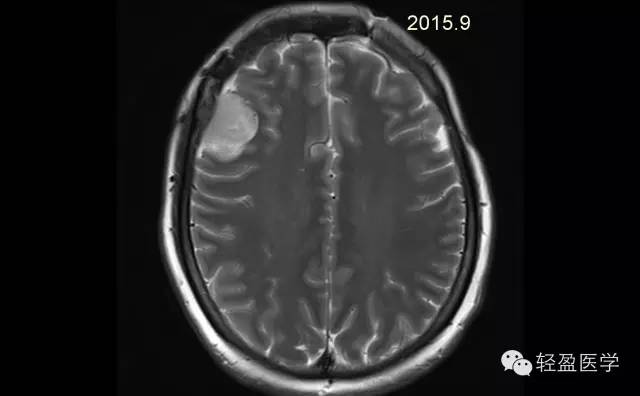

【病例】颅内肿瘤,脑内?脑外?

病理为:小细胞恶性肿瘤,考虑为(外周)原始神经外胚层肿瘤,(复发)。以下是病例结果及分析。